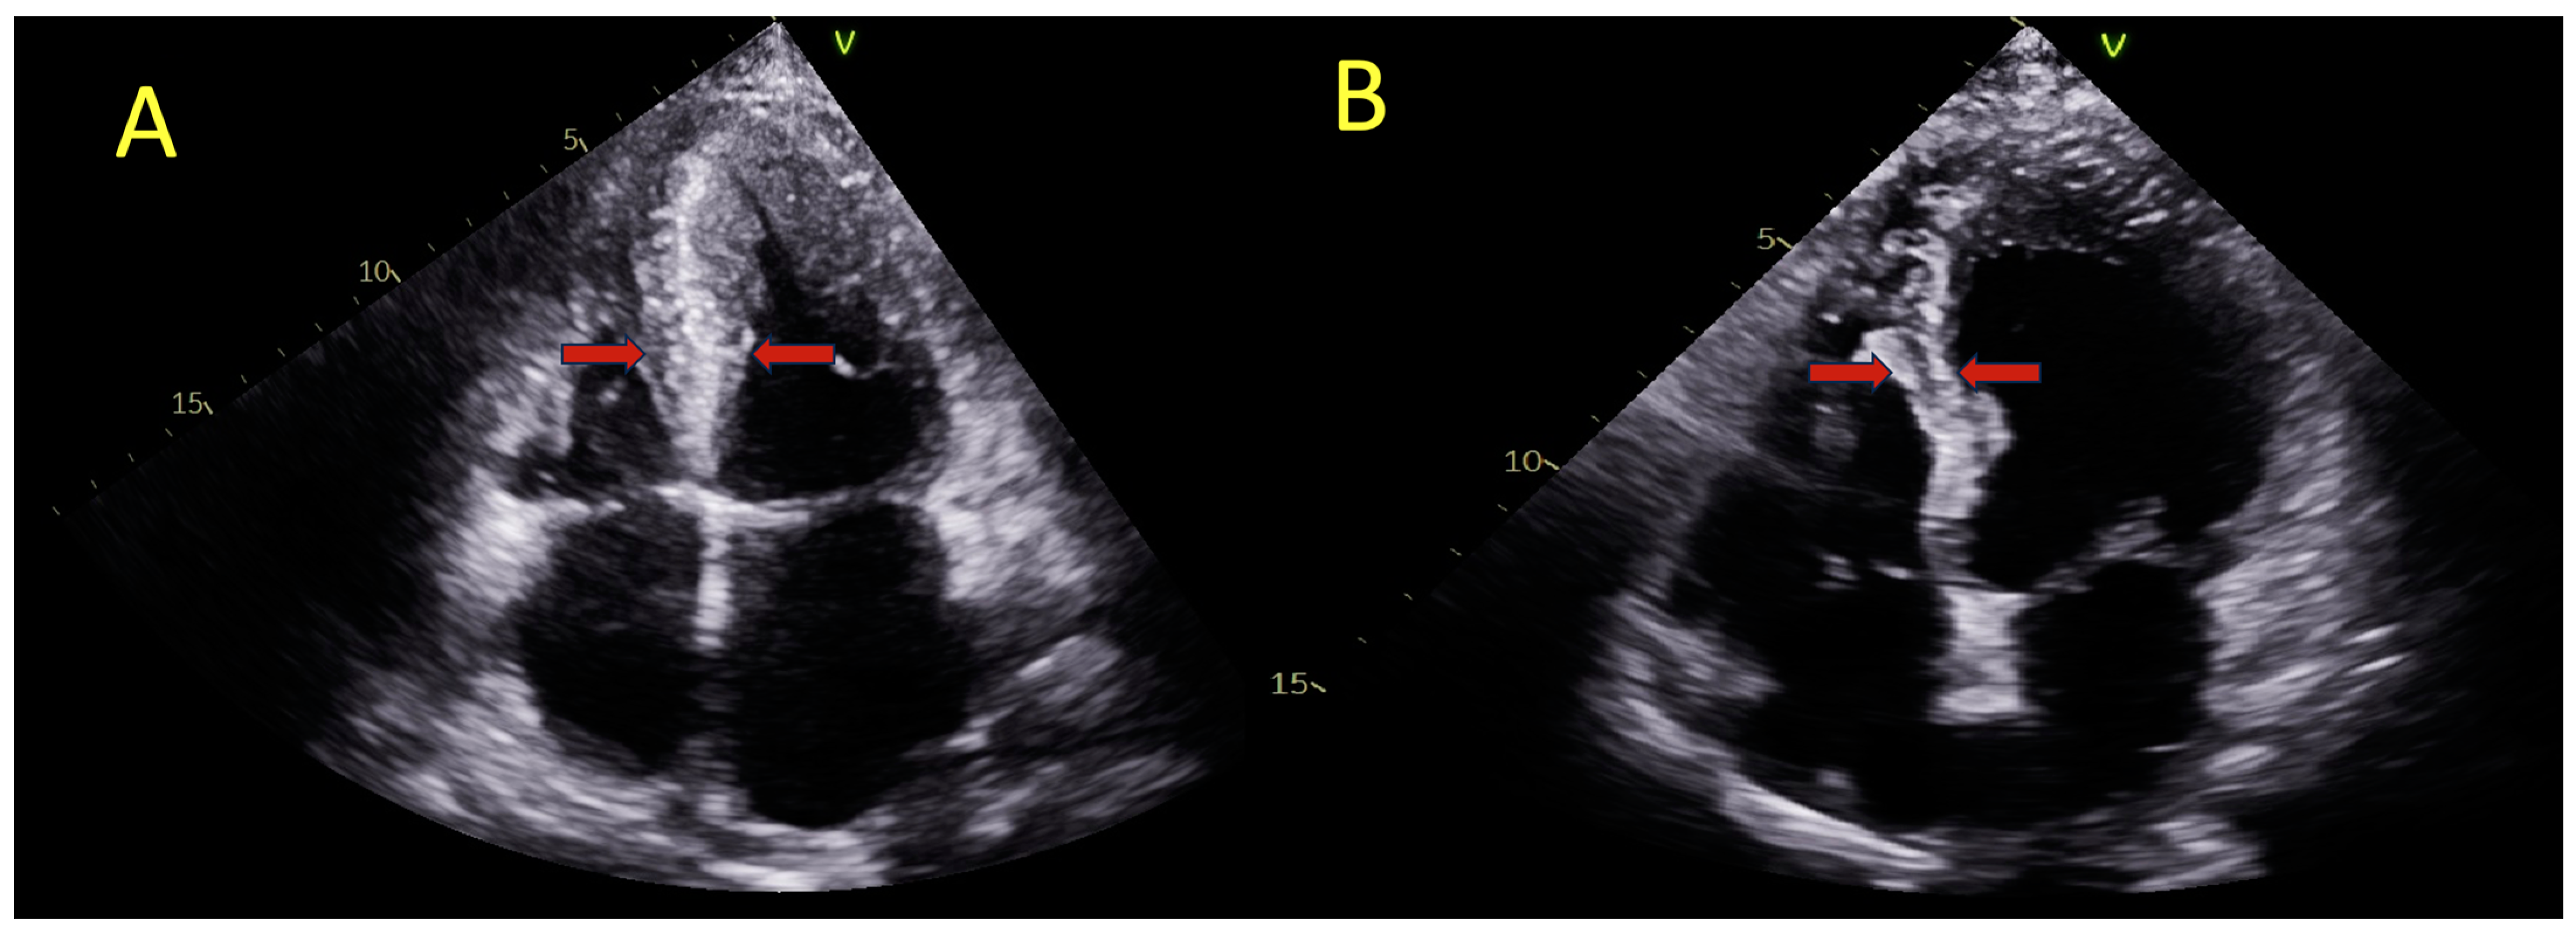

1. Introduction

2.2. Two-Dimensional and Speckle-Tracking Echocardiography